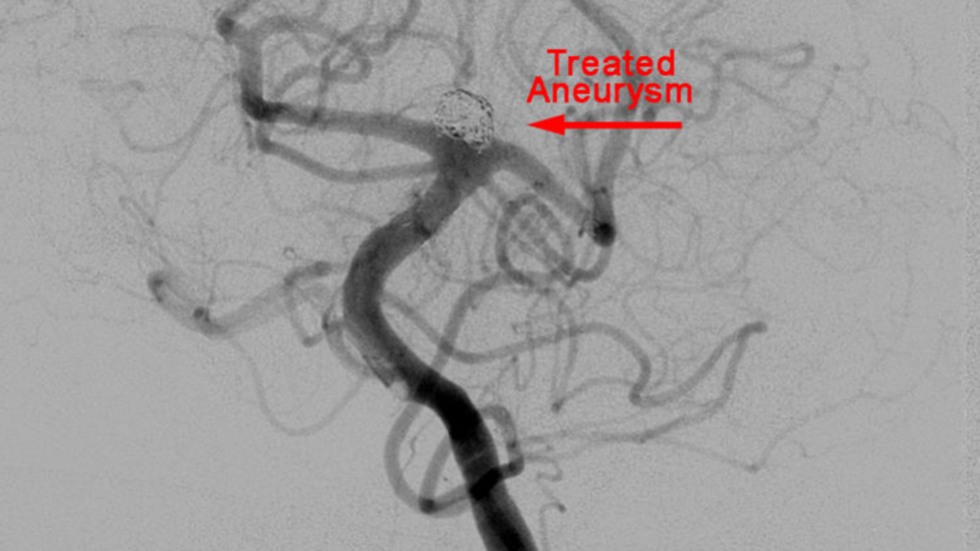

Technique: Treated Aneurysm

3 of 3